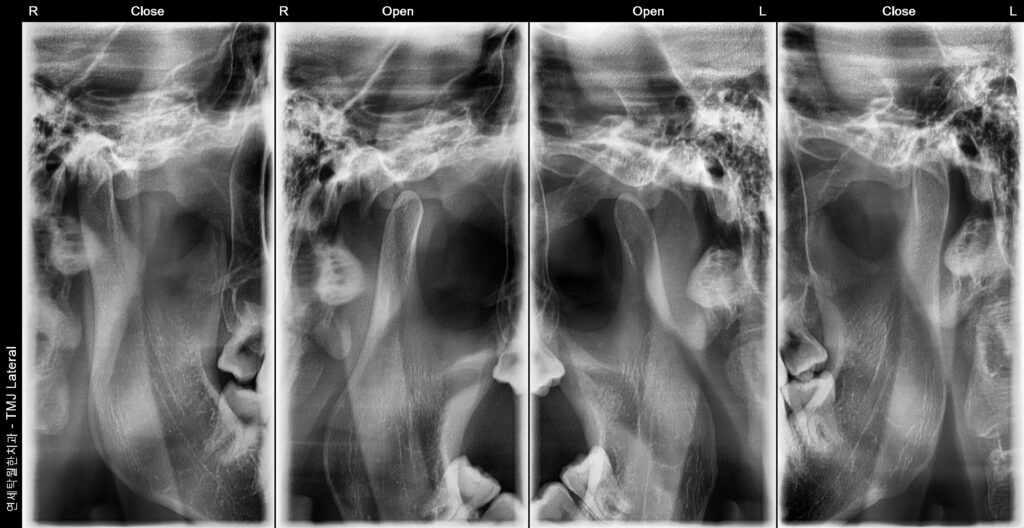

[원장칼럼]”턱관절이 아픈데 어디로 가야하나요?” (정형외과? 한의원? 정답은 ‘치과’입니다!)

“턱관절이 아픈데 어디로 가야하나요?” (정형외과? 한의원? 정답은 ‘치과’입니다!) 안녕하세요! 청주 연세탁월한치과입니다. 아침에 일어났을 때 턱이 뻐근하거나, 입을 벌릴 때마다 턱에서